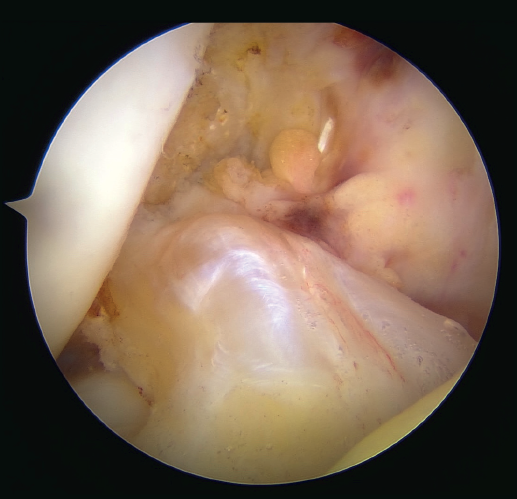

The patient is placed in the supine position and the leg is draped and prepared for knee arthroscopy at the surgeon's discretion, as if an ACL plasty were to be performed. The anterolateral and anteromedial portals are established as usual, and the joint is explored. On exploring the central compartment, it should be confirmed by direct vision and also palpation that the lesion is proximal and that the tissue quality is good; if the tissue is friable and tears easily, repair is not indicated. If the ACL remnant is attached to the PCL, it must be dissected so that the ACL is free and can be manipulated to its insertion site. A blunt shoulder arthroscopy periosteotome is best used for this, although a synoviotome, vaporizer or plasma applicator could also be used, as long as care is taken not to break or burn the tissue and render it non-viable. If there are concomitant meniscal or cartilage lesions, they should be treated earlier in order to avoid forced varus and valgus positions after the repair is completed.

Once a good view of the central compartment is obtained, the area of the femoral footprint of the ACL is prepared to leave exposed bone, and microperforations are made in the medial wall of the lateral condyle to leave a bleeding bed to favor healing of the ligament (Figure 3). These microperforations can be made using specific instruments or with the implant punch. The advantage of using the punch is that the implant insertion site can be prepared at the same time, and only one instrument is used for the entire process (Figure 4). This step can be done after the suture has been prepared in the ligament, although doing it beforehand avoids the threads from standing in the way. The ideal point for fixation is just anterior to the native ACL footprint, although if the tear is partial or corresponds to Sherman I, it can be taken to the anatomical footprint without difficulty.